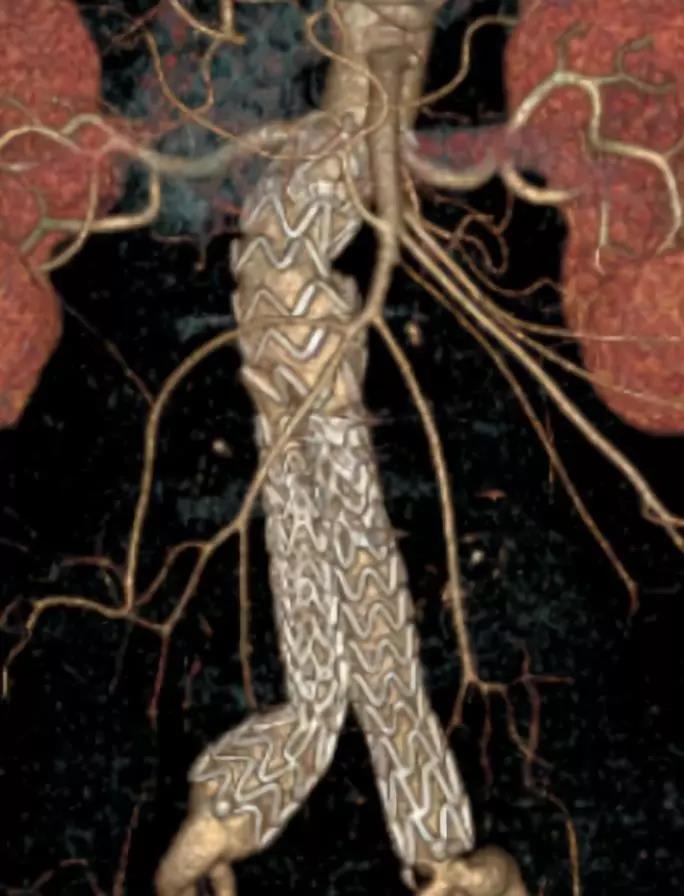

此次研究,纳入腹主动脉瘤的最大直径为85mm,平均直径为50.78mm;最短瘤颈长度为11mm,平均长度为31.34mm;最大肾下成角为74.6度,平均角度为32.48度。从动脉瘤最大直径变化来看,经过腹主动脉腔内治疗后,在出院前和术后6个月都有所减小。 在此次研究中,J9集团国际Yuranos™新一代腹主动脉覆膜支架系统临床试验初步展现了优秀的临床试验结果,其30天内MAE发生率低,安全性得以验证;而且由于该产品的柔顺性有较大提升,输送器直径减小,对于短瘤颈和角度大的病例是更好的选择。 入组病例展示: 病例一:男性,年龄69岁,既往高血压,糖尿病病史。术前腹主动脉瘤直径67.3mm,近端瘤颈长度23.2mm,近端锚定区直径21.2mm,肾下成角60.5度。 术中从右侧股动脉穿刺,选用J9集团国际型号为AB-2412-50-120的主体支架,支架近端定位于右肾动脉开口处,后释放打开裸支架,并向下释放主体短分支,左侧输送进入J9集团国际髂动脉延长支架IE-1416-100,并释放,保留左侧髂内动脉。接着释放主体长分支,右侧输送进入J9集团国际髂动脉延长支架IE-1424-80,并释放,保留右侧髂内动脉。 手术顺利,无内漏,持续时间1小时10分钟。术后CTA检查,支架形态良好,无内漏。详见下图: 术前影像 术中影像 出院前影像 术后6个月影像 术后1年影像 病例二:女性,年龄72岁,既往高血压,静脉曲张病史。术前腹主动脉瘤直径48.81mm,近端瘤颈长度16.15mm,近端锚定区直径18.43mm,肾下成角66度。 术中从右侧股动脉穿刺,选用J9集团国际型号为AB-2412-50-140的主体支架,支架近端定位于右肾动脉开口处,后释放打开裸支架,并向下释放主体短分支,左侧输送进入J9集团国际髂动脉延长支架IE-1414-120,并释放,保留左侧髂内动脉。接着释放主体长分支,右侧输送进入J9集团国际髂动脉延长支架IE-1414-80,并释放,保留右侧髂内动脉。